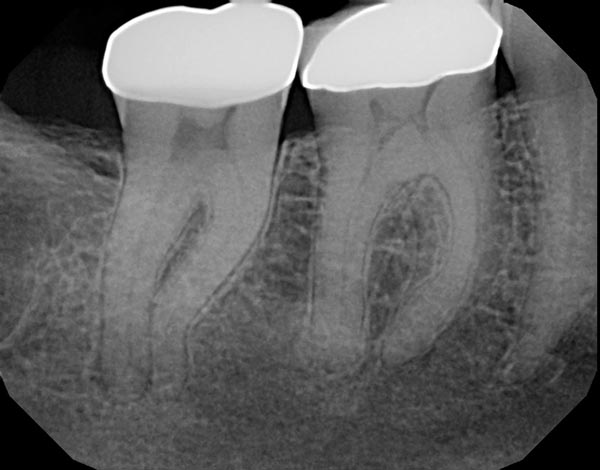

Fig. 2a: A distal angled preoperative image shows a well-defined radiolucency at the MB root apex and the previous root filling is off center, suggesting an untreated ML canal. Fig. 2b: An axial view of a CBCT clearly demonstrating the missed ML canal. Fig. 2c: Re-treatment was completed and the final shape of the canals was achieved using WaveOne Gold from Dentsply Sirona, a reciprocating, single file system that has a variable taper. Fig. 2d: At six-month recall, the tooth was asymptomatic and bone healing was complete as the PDL space and trabecular pattern were normal.

Fig. 2a

Fig. 2b